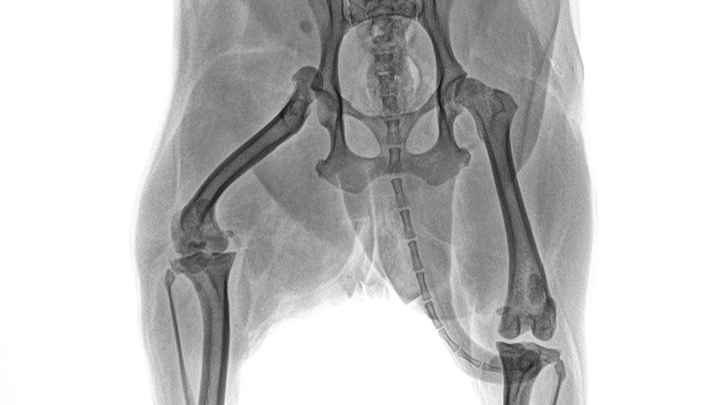

El pasado 14 de noviembre, en mi domicilio, un vecino atropelló accidentalmente a Dalia y se dio a la fuga, dejándole una luxación en una de sus patitas. La lesión fue tan grave que requirió una cirugía ortopédica inmediata. Hasta el 22 de noviembre, los gastos médicos acumulados llegaron a casi $40,000 MXN, los cuales logré cubrir parcialmente gracias al apoyo de amigos y familiares.

Seguimos al pie de la letra el tratamiento indicado por los veterinarios de Animal Home San Jerónimo, pero lamentablemente, el 10 de diciembre recibí una noticia devastadora: además de la luxación, Dalia presenta una rotura de ligamento cruzado y posibles daños en los ligamentos laterales.

El nuevo diagnóstico exige otra cirugía urgente, con un costo estimado de $30,000 MXN, lo que elevaría el total de gastos médicos a poco más de $70,000 MXN.